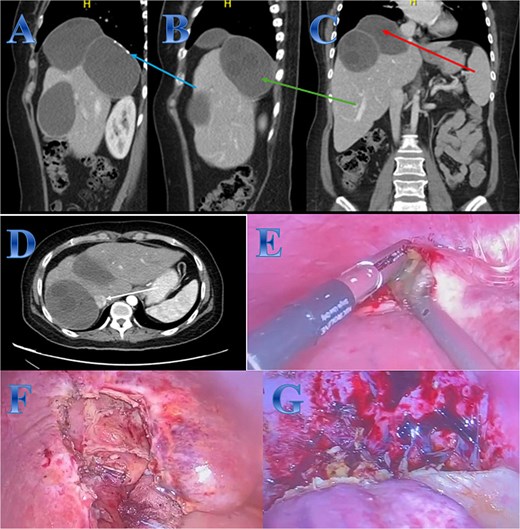

A 31-year-old male presented with a 5-days history of epigastric pain accompanied by jaundice, darkened urine, together with a clay stool. On examination, there was jaundice with epigastric tenderness. Clinical tests showed increased total and direct bilirubin levels. CT showed left hepatic lobe exophytic CE (Fig. 4).

Case 4. (A & B) Post-contrast CT cuts showing well-defined cystic lesion showing internal daughter cysts noted at the left hepatic lobe and seen exophytic indenting the lesser curvature of the stomach, septate lesion is seen in the left lobe of the liver (photo A). The lesion is abutting the lesser curvature of the stomach with intact fat planes between the two (photo A). (C & D) MRI cuts showing well-defined, septate lesion, abutting the lesser curvature of the stomach. The lesion makes some mass effect off the left hepatic biliary radicles communicating with the lesion (photo C).

The patient underwent ERCP for biliary drainage. Subsequent follow-up revealed improved jaundice and reduced pain; at that time, the patient was started on albendazole, which continued for 2 months. The patient was admitted for surgery, and laparoscopic left lateral resection was done. After liver mobilization was done by detaching the falciform, left triangular and coronary ligaments to mobilize the left liver lobe. Retraction of the left lateral segment was performed to expose segments 2 and 3 which were isolated using laparoscopic gauze soaked in hypertonic saline A harmonic scalpel was used for parenchyma transection, and the left bile duct was identified between segments 4 and 2 and 3, which was transected using endovascular gastrointestinal stabler (endo-GIA). Before ending the parenchyma dissection upward, the left hepatic vein was identified and divided using endo-GIA (Fig. 4).